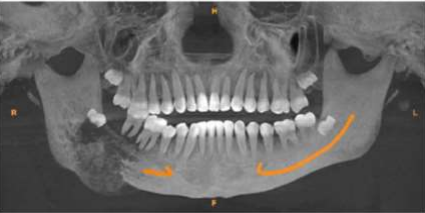

Fig 1: Aggressive soft tissue growth in the posterior mandibular region with displacement of involved teeth.

Figure 5: ulcerative lesion of the right posterior region of the jaw

A 13- year old male patient presented with a painless rapidly enlarging growth of the right posterior region of jaw since 2 months. Intra-oral examination revealed a firm, non-tender reddish soft tissue mass in the right posterior mandibular region extending anteriorly from 45 to retromolar region posteriorly involving the buccal and lingual mandibular gingiva. Inferiorly the lesion extended till the floor of the mouth causing displacement of the tongue along with displacement of the associated teeth (Fig 1). Radiographically, an ill-defined osteolytic lesion of the right posterior mandible with buccal and lingual cortical plate expansion was noted (Fig 2).

A 14-year old female patient reported with an ulcerative lesion of the right posterior region of the jaw associated with mobility of teeth 46 and 47 since 1 month (Fig 5). The patient was apparently normal 1 month back after which the lesion was noted. CBCT shows a solitary large ill-defined expansile osteolytic lesion of mixed density in the region extending from 46 to the right body and ramus of the mandible (Fig 6). A provisional diagnosis of aggressive neoplastic lesion such as odontogenic myxoma and osteosarcoma was considered. Incisional biopsy was performed and the H and E stained sections shows sheets of malignant tumor cells separated by fibrous connective tissue septae. The malignant cells displayed atypical features such as cellular and nuclear pleomorphism, nuclear hyperchromatism and few bizarre shaped cells. Presence of eosinophilic areas resembling tumor osteoid surrounded by malignant osteoblasts was evident. In addition, the sections also showed a sub-population of clear cells which were round to oval in shape with vesicular nuclei and clear cytoplasm with some binucleation resembling chondroid like areas (Fig 7 & 8). Special staining for PAS and mucicarmine to rule out clear cell odontogenic carcinoma and intra-osseous mucoepidermoid carcinoma was negative. Based on these findings the final diagnosis was chondroblastic variant of osteosarcoma. Hemimandibulectomy was performed and the final diagnosis of the excised specimen was high grade osteosarcoma. Six month follow-up was uneventful.